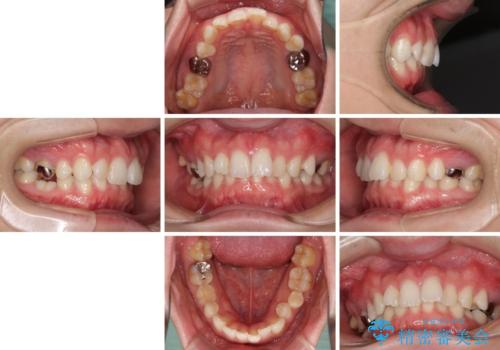

- 咬み合わせと前歯のデコボコを気にして来院された患者様です。

前から5番目の永久歯が3本欠損しており、乳歯が残存している状態でしたが、インビザラインでも十分に対応可能と判断し、インビザラインにて矯正治療を行うこととしました。

右下の残存している乳歯は萌出しきれておらず、全く咬み合っていない状態であり、インビザラインにて移動できない可能性があるため、ワイヤー矯正の併用も念頭に置いて治療を開始しました。

萌出が不十分な歯はインビザラインで引き出すことができないため、ワイヤー装置などの併用が必須となります。

今回は部分的にワイヤー矯正を用いましたが、右下の乳歯は全く動かなかったため、抜歯をした上でインプラントを埋入し、オールセラミッククラウンにて補綴治療を行いました。